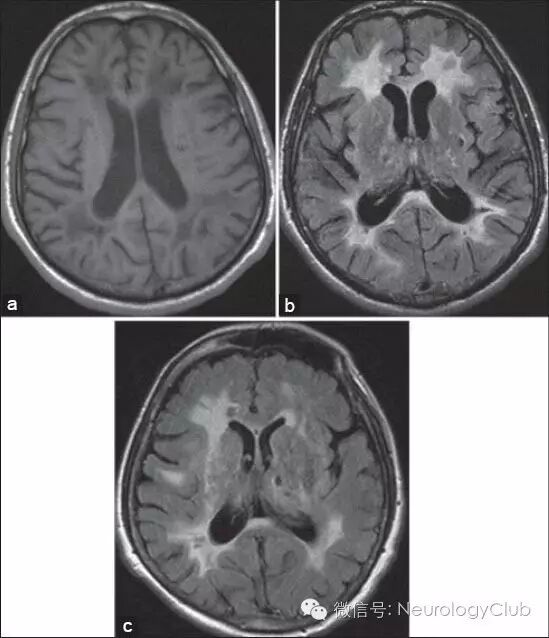

(图5:A:T1WI可见脑室旁低信号病灶;B-C:FLAIR可见脑室旁高信号病灶,外囊受累,基底节区可见腔隙性梗死)